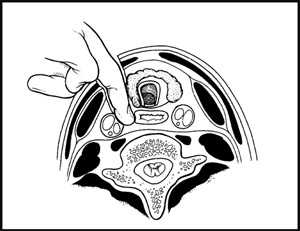

С этого этапа мною используется хирургический микроскоп, позволяющий различать все нервные структуры под увеличением до 16 раз. Это позволяется работать с тканями очень аккуратно, не допуская излишнего травматизма. Вначале удаляется мп диск, а затем и сама грыжа. (Рис.3) Операция заканчивается установкой межтелового импланта - кейджа (протеза диска). Кейдж (в переводе с английского «cage» означает «сетка») представляет собой титановый или пластиковый имплант, заполняемый собственной костной крошкой пациента или другим остеоиндуктивным (костеобразующим) материалом. Кейджи устанавливаются в полость диска, в результате чего восстанавливается высота последнего и соответственно высота фораминального отверстия (через который выходит спинномозговой корешок из позвоночного канала) для исключения сдавления корешка в указанном месте.

| Рис.3. Этап удаления грыжи мп диска вместе с диском. |